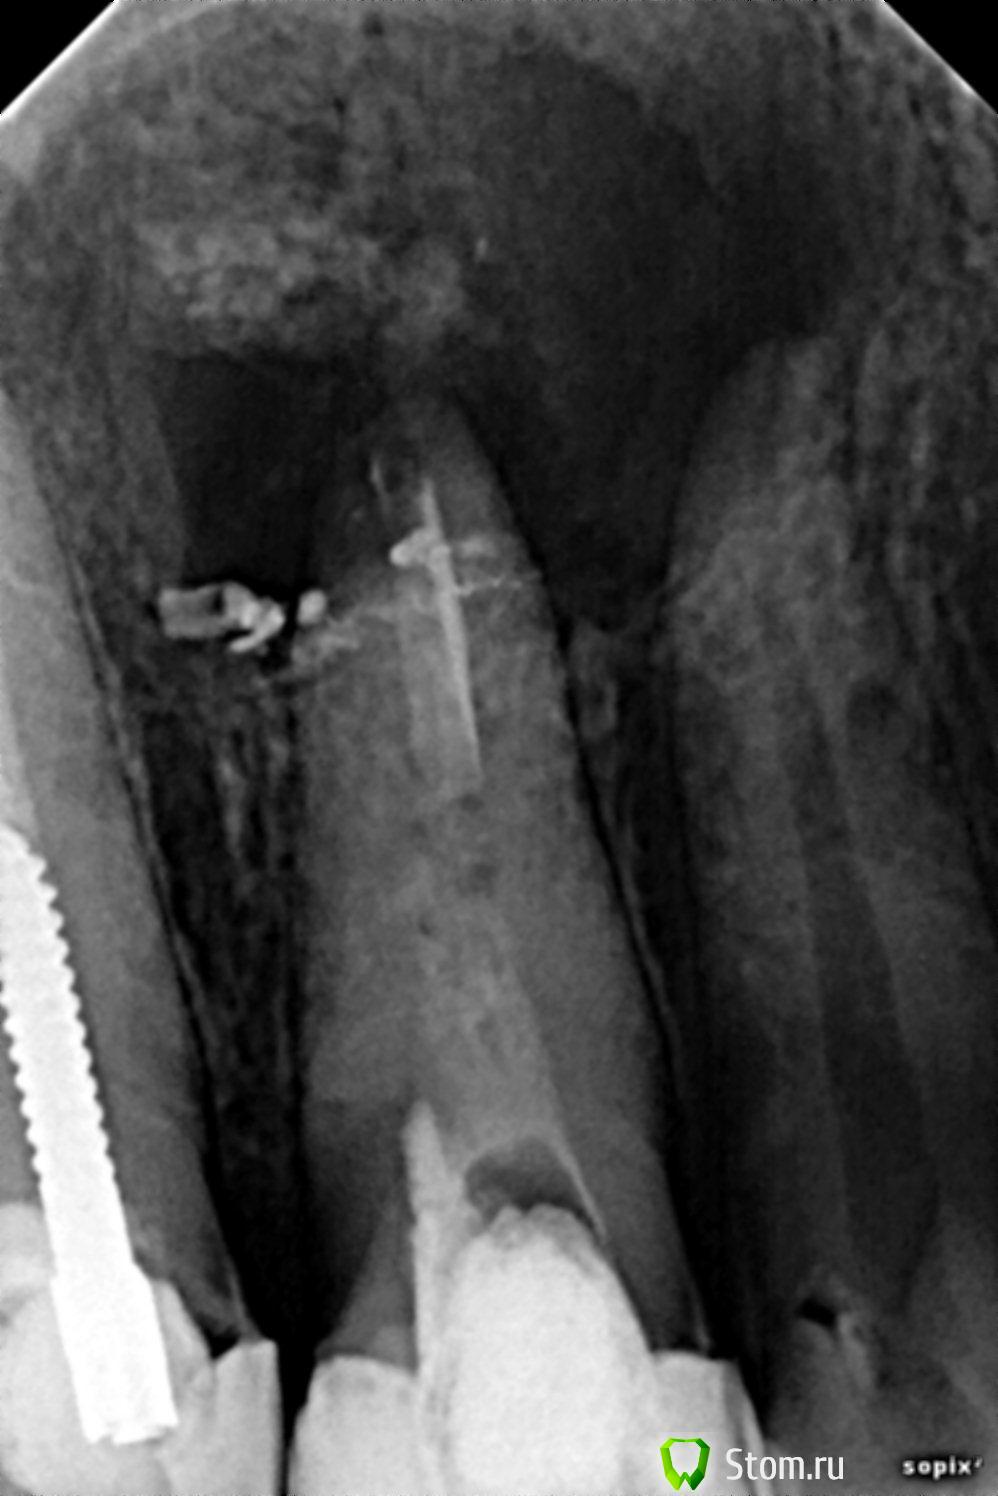

aleksisAG Опубликовано 7 апреля, 2012 Поделиться Опубликовано 7 апреля, 2012 Пациент 30 лет,женщина,6 месяцев 21 под "каласептом",свищь Ссылка на комментарий

viruzzz Опубликовано 7 апреля, 2012 Поделиться Опубликовано 7 апреля, 2012 а почему в разжеле "хирургическая стоматология"?есть микрофлора, устойчивая к калосепту. Канал до конца пройден? что за остатки пломбировочного материала (ифицированного уже долгое время) в апикальной части? Ссылка на комментарий

red_butler Опубликовано 9 апреля, 2012 Поделиться Опубликовано 9 апреля, 2012 Проведите ЭОД на 2.2 - по снимкам он в дефекте. Далее КТ. Затем скорее всего постоянное эндо 2.2 2.1 и цистэктомия. Ссылка на комментарий